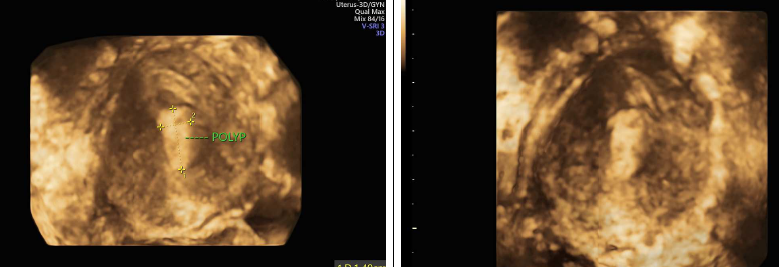

4D PELVIS ULTRASOUND IN ROHINI DELHI A 4D pelvic ultrasound is a type of ultrasound that uses real-time images to show the movement of the pelvic floor muscles. It can be used to assess pelvic organ prolapse and incontinence.